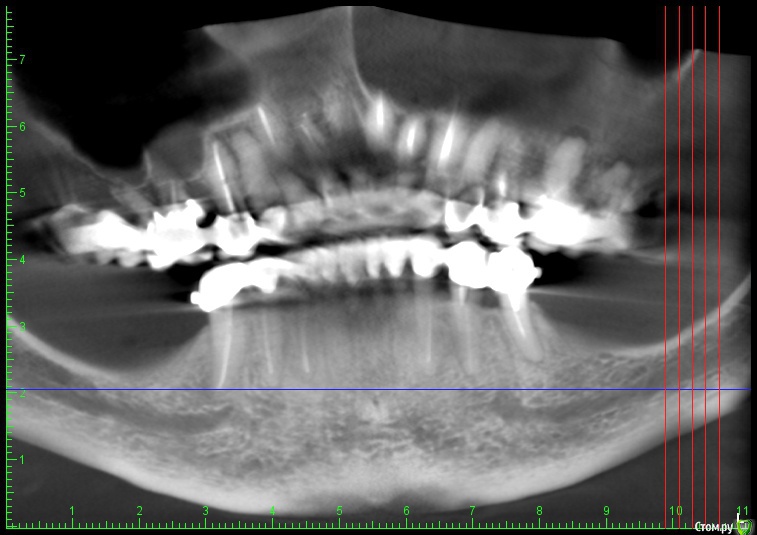

an_ver Опубликовано 17 января, 2016 Поделиться Опубликовано 17 января, 2016 (изменено) Верхние винты насквозь через SP и в свою кость? Как горизонтальный распил делаете, пальцем с язычной, тактильно? Пилите УЗ?И есть ли снимок до? Изменено 17 января, 2016 пользователем an_ver Ссылка на комментарий

Глеб Митрофанов Опубликовано 19 января, 2016 Автор Поделиться Опубликовано 19 января, 2016 Верхние винты насквозь через SP и в свою кость? Как горизонтальный распил делаете, пальцем с язычной, тактильно? Пилите УЗ?И есть ли снимок до?Верхние винты в свою кость , распил делал УЗ , язычно контроль пальпаторно , да и чувствуется , что прошёл язычную кортикалку . Снимок до конечно есть . Ссылка на комментарий